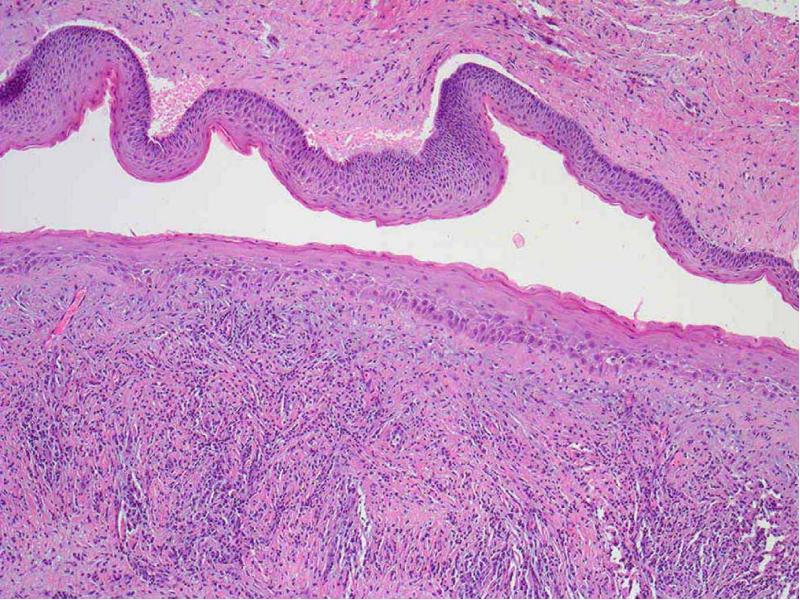

- 23. Микроскопическая картина Имеет тонкую фиброзную стенку с выстилкой из многослойного плоского